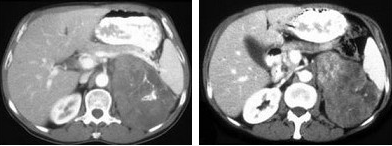

女,43岁,满月脸,皮肤紫纹、月经不规则3月余,请结合所提供图像,作出诊断( )

A:左肾上腺腺瘤

B:左肾上腺嗜铬细胞瘤

C:左肾上腺转移瘤

D:左肾上腺腺癌

E:左肾上腺增生